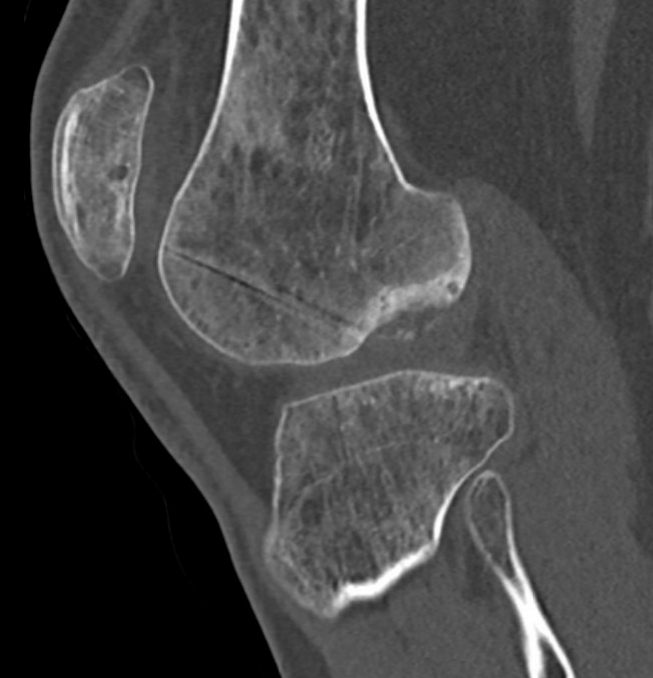

CT

Osteochondral defect